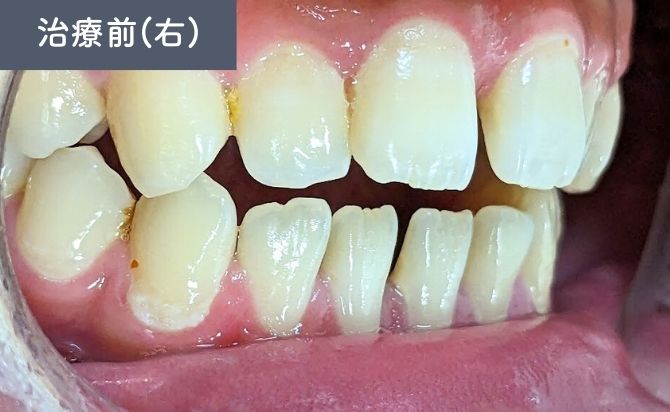

診察では、上顎左右1番間の歯間空隙(すきっ歯)が認められ、審美面での改善希望が強い症例でした。また、前歯部では上下の噛み合わせが接触しない開咬(オープンバイト)の状態が確認されました。

上下前歯には軽度の前突傾向があり、歯列弓の乱れによって歯間空隙と噛み合わせの不安定さが生じている状態でした。

臼歯部の咬合は比較的安定しており、前歯部を中心とした矯正治療で十分な改善が見込める症例と判断しました。

歯並びの変化(右)